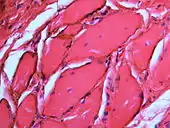

Granular deposits of silver sulfide along elastic fibers of the connective tissue of the oral mucosa. Low chronic inflammatory changes in the form of a lymphocytic aggregate (bottom right)

If necessary, the diagnosis can be confirmed histologically by excisional biopsy, which excludes nevi and melanomas.[3]:138 If a biopsy is taken, the histopathologic appearance is:[1]

• Pigmented fragments of metal within connective tissue

• Staining of reticulin fibers with silver salts

• A scattered arrangement of large, dark, solid fragments or a fine, black or dark brown granules

• Large particles may be surrounded by chronically inflamed fibrous tissue

• Smaller particles surrounded by more significant inflammation, which may be granulomatous or a mixture of lymphocytes and plasma cells